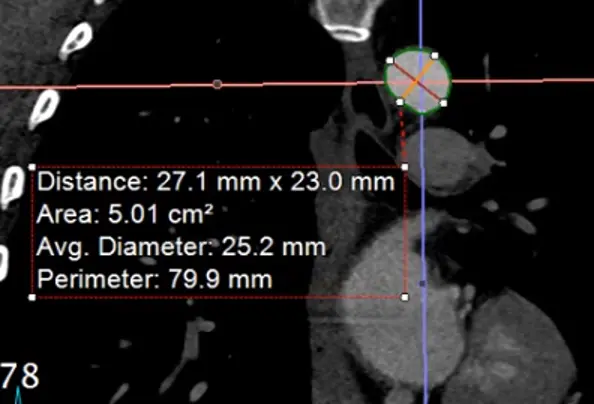

Measure at Sinotubular Junction

- Drag the lines to the sinotubular junction, i.e. where the sinuses and the tubule combine

- In the axial view, the âtrue short axisâ should be pretty close to appearing like a circle.

- đ Hit

- Hit

Alt+Dto automagically measure - Right click and Capture to stash the image and measurement